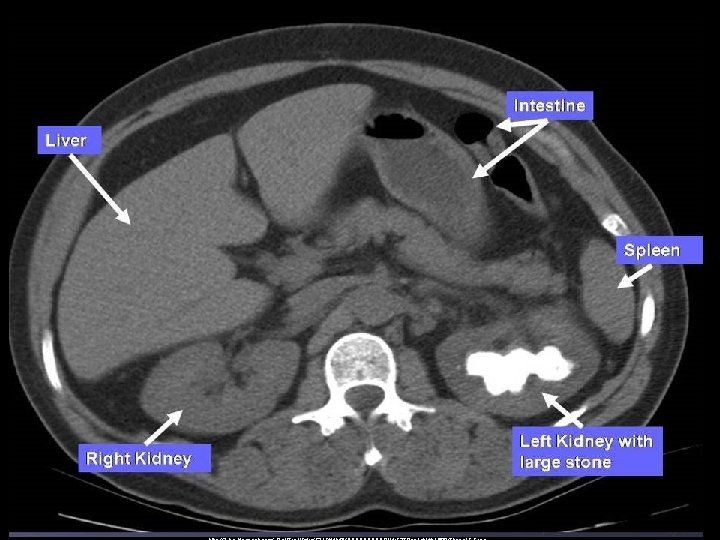

Vyšetření ledvin • • nativní rtg snímek sonografie vylučovací urografie ascendentní pyelografie scintigrafie clearence CT, MR

http: //www. kidneystoners. org/wpcontent/uploads/2012/02/pediatrickidney-stone-CT. jpg

Nemoci ledvin • vývojové vady • cysty (solitární x polycystické ledviny) • ren migrans (bloudivá ledvina) • glomerulonefritis • pyelonefritis • nefrolitiáza • renální kolika • hydronefrosis • diabetes mellitus – nefropatie • nádory • Grawitz (solitární metasázy) • Wilms (autozomálně dědičný – děti) • stenóza a. renalis

Nefrolitiáza